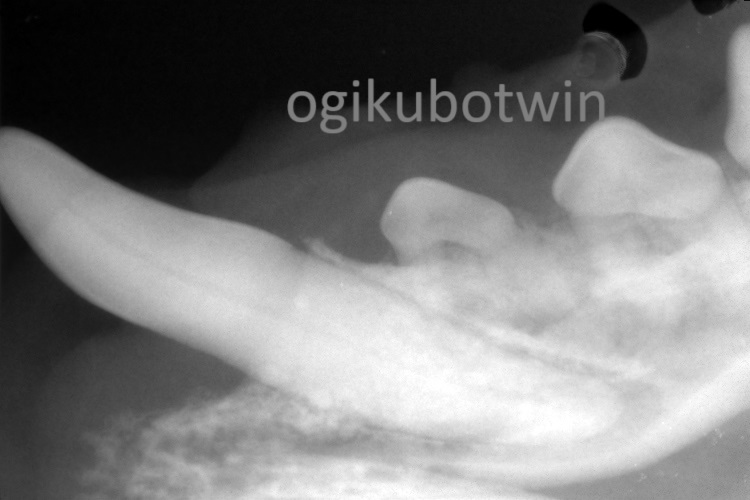

全身麻酔下にてレントゲンを撮影し歯の状況を確認しました。

2年4か月後に鎮静下にてレントゲンを撮影しました。

歯磨きは継続して行って頂きましたが歯周病が進行し、ポケットの深さは6㎜程になっていました。

このままでは抜歯しなければならない状態が予想されたので、再度全身麻酔をかけて歯のクリーニングを行いました。